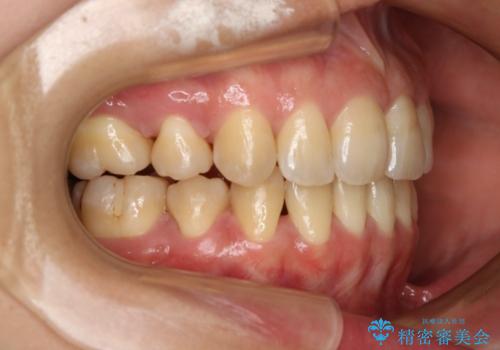

抜歯を行うことで前歯を後ろへ下げるスペースを獲得し、口元の突出感や歯のガタつきを改善していきました。

- 前歯を後ろへ下げることを主訴に来院された患者様です。

口元の突出感の改善や歯の移動量などを考慮し、抜歯を伴うワイヤー矯正での治療を選択しました。